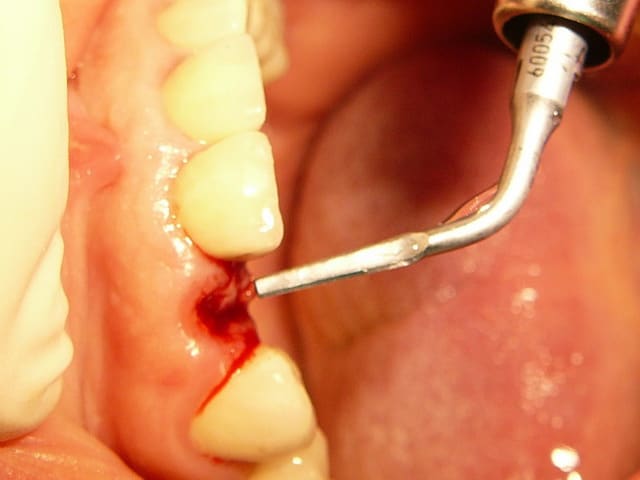

au cas où vous ne fait la provisoire immediatement, vous pouves choisir le" one stage procedure" . Dans ce cas, vous conservez la profile de la gomme avec une "gingiva former".

dans la zone estetique e tres important a fere extraction atraumatique e forage palatine pour preserver l os vestibularie.

le placement du implant doivent suivre( respecte) les règles de "3D insertion in estetic zone".

je vous recomendextraction avec la piezo.( piezotome satelec-est que ce j utilise)

prothèse définitive après 6 mois